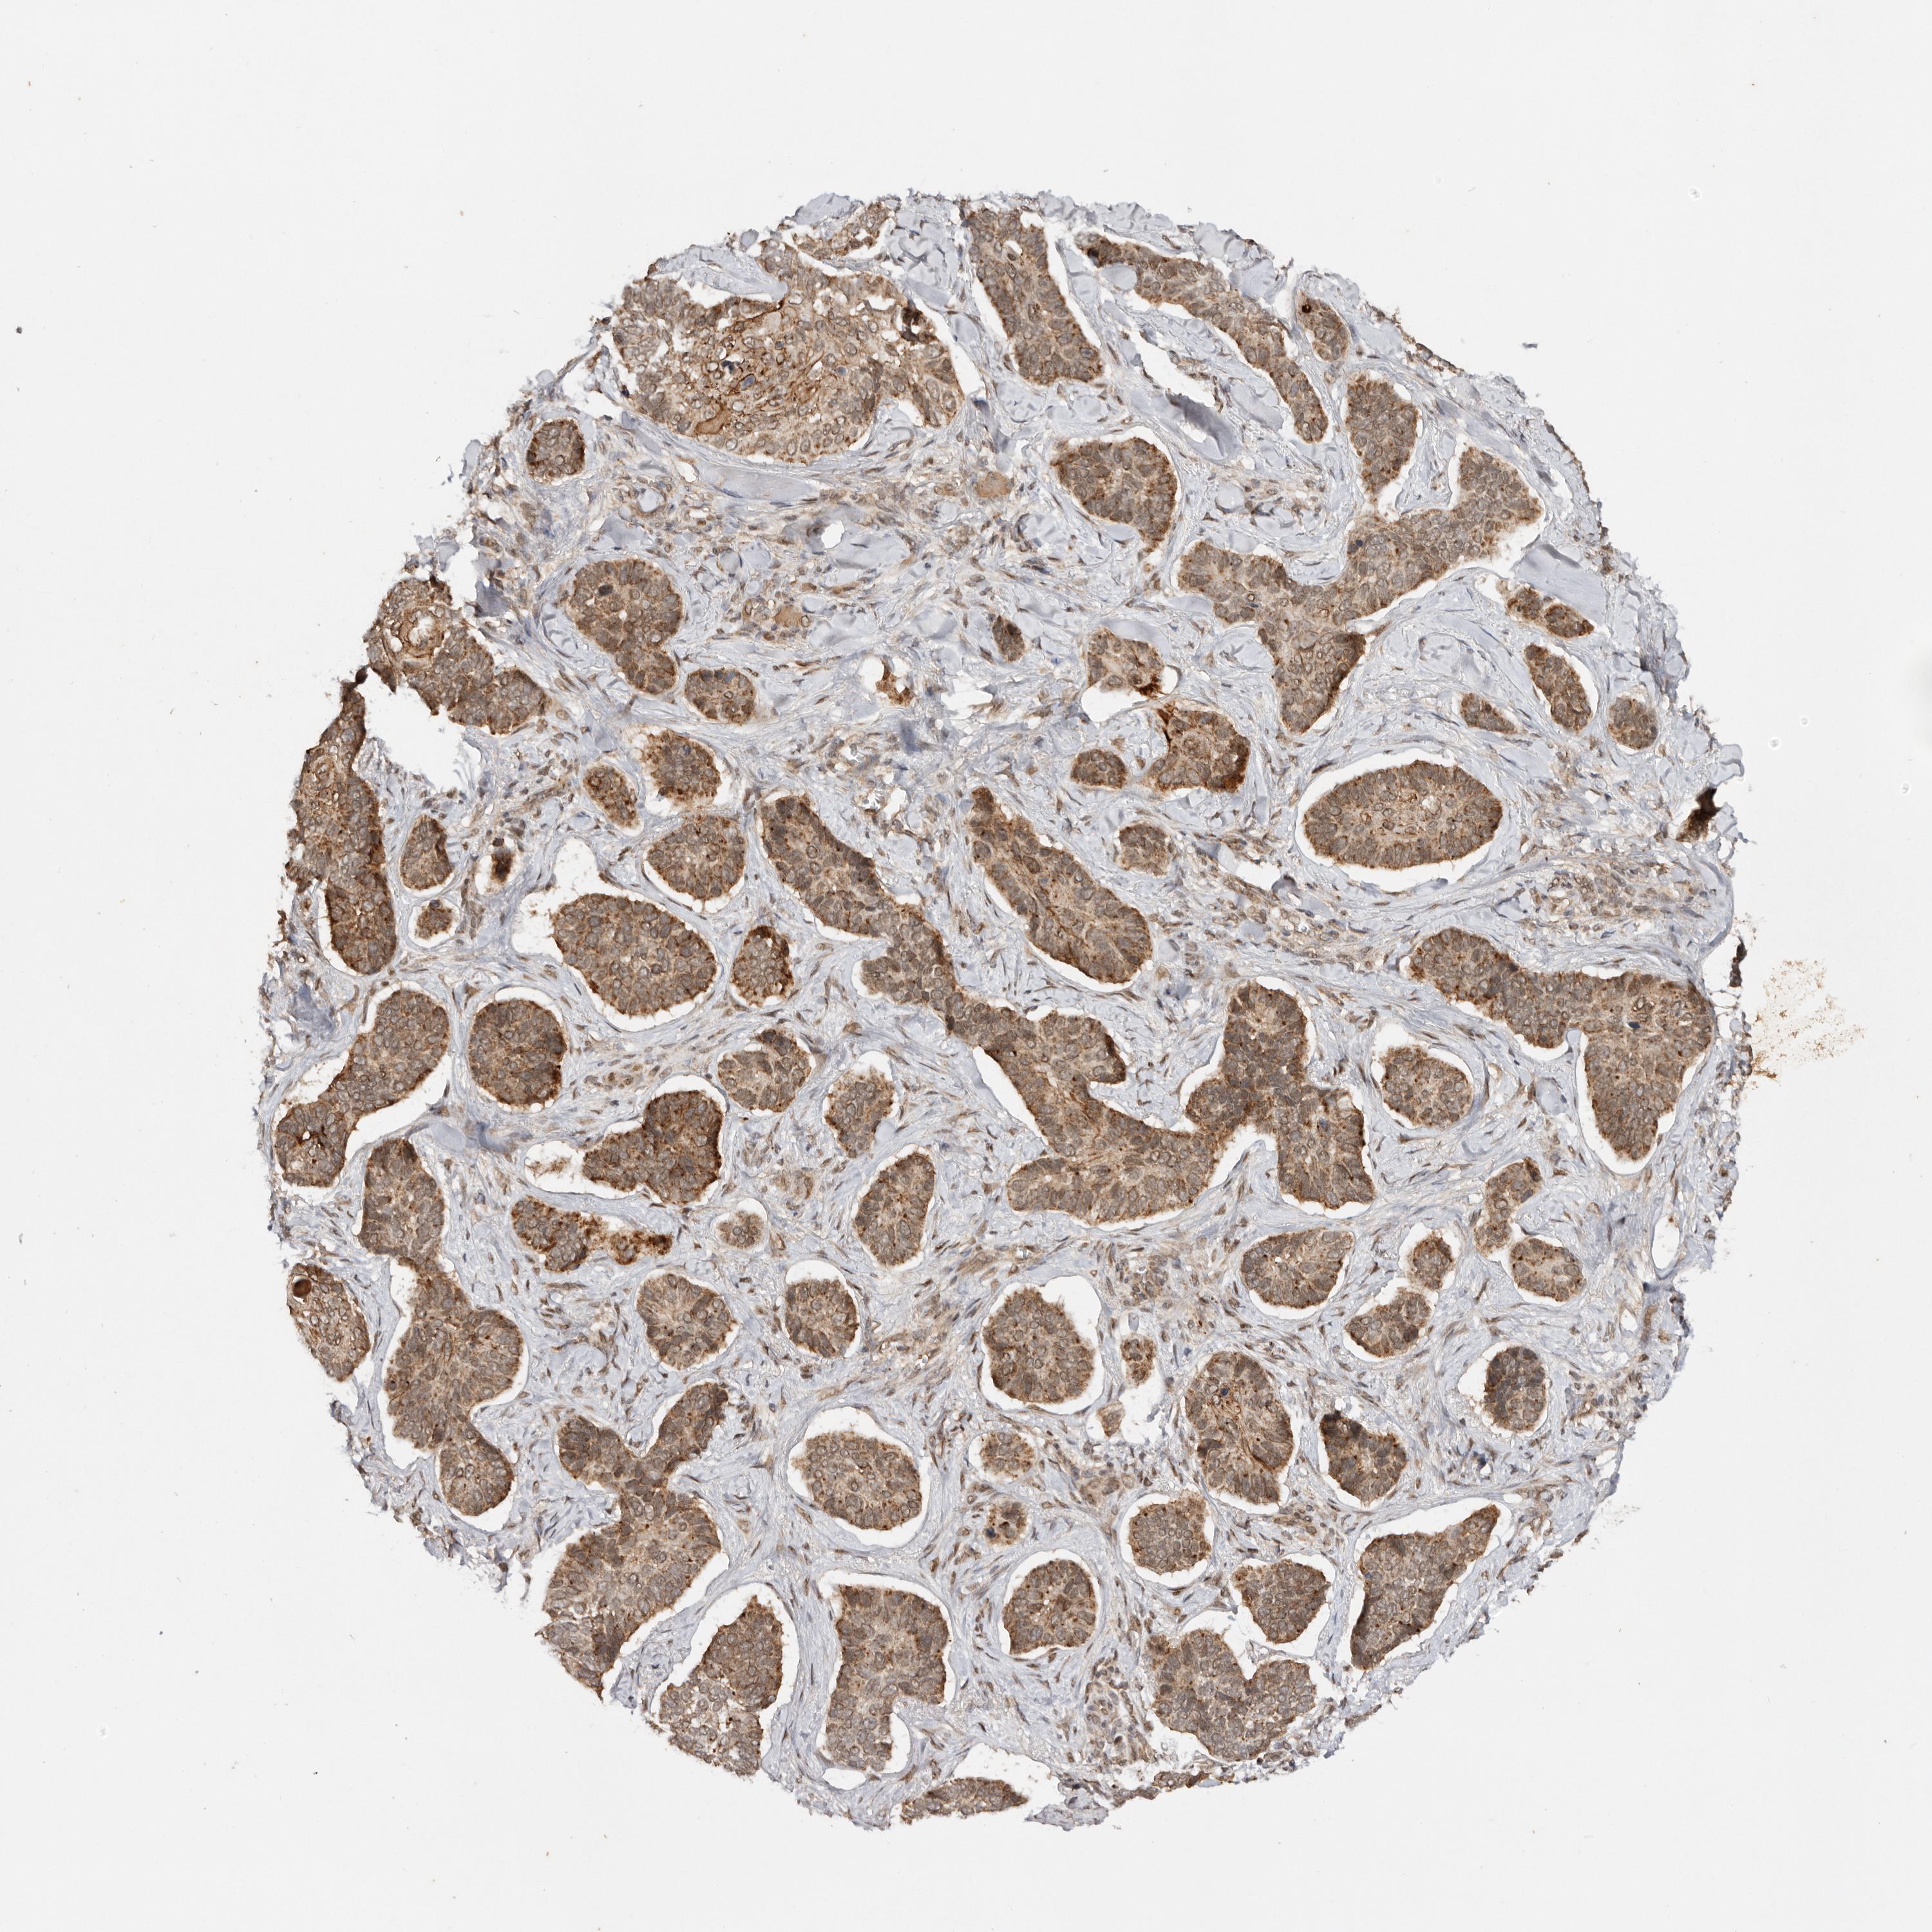

SKIN CANCER - Protein expressioni

A mouse-over function shows sample information and annotation data. Click on an image to view it in a full screen mode. Samples can be filtered based on level of antibody staining by selecting one or several of the following categories: high, medium, low and not detected. The assay and annotation is described here.

Antibody stainingi

Antibody staining in the annotated cell types in the current human tissue is reported as not detected, low, medium, or high, based on conventional immunohistochemistry profiling in selected tissues. This score is based on the combination of the staining intensity and fraction of stained cells.

Each image is clickable and will lead to virtual microscopy that enables deeper exploration of all samples and also displays staining intensity scores, fraction scores and subcellular localization as well as patient and tissue information for each sample.

Antibody HPA028626

Staining

High

Strong

Quantity

Location

Basal cell carcinoma